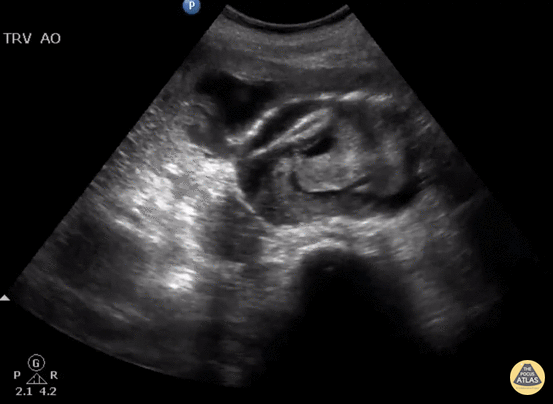

Aorta - Ruptured AAA with Active Hemorrhage

Elderly female presents to ED with back pain and hypotension. Bedside US shows a ruptured AAA with active hemorrhage in the 9 o’clock position. Image courtesy of Robert Jones DO, FACEP @RJonesSonoEM Director, Emergency Ultrasound; MetroHealth Medical Center; Professor, Case Western Reserve Medical School, Cleveland, OH View his original post here